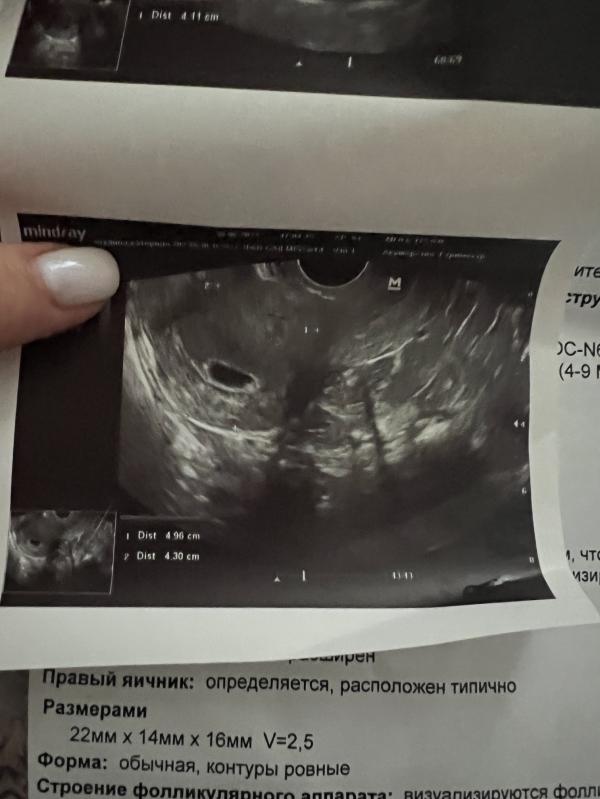

У меня срок +- 5 недель 5 дней, пока видят только плодное яйцо 13,4мм. Вот теперь накручиваю себя что может оно вообще пустое(( хоть и понимаю что наверное ещё рановато

У меня в вторник вообще плодное яйцо было 4мм, а это было 5 и 3

Я вот переживаю,что у меня плодное яйцо растет(13,4 мм), в среду было 9мм, а жм не видят(

Желточный мешок видели при 9 мм диаметре плодного яйца.

Извините, но у вас видно желточный мешочек невооружённым глазом, почему вам написали не визуализинуетсч?

А фиг ее знает, сказала отчетливо не вижу, в другом клинике где делала сказали что видят задатки,но измерить пока не могут

@katmorii да да, у меня точно такая же картина. ЖМ у меня слева был. Но на узи сказали его нет. А в группе односрочниц все подтвердили наличие жм

@katmorii оно похоже на маааааленькое колечко с каратом на вашей картине.

А желточный мешок тоже не видели? Просто врач узи ещё напугала,что желточный мешок уже должен быть